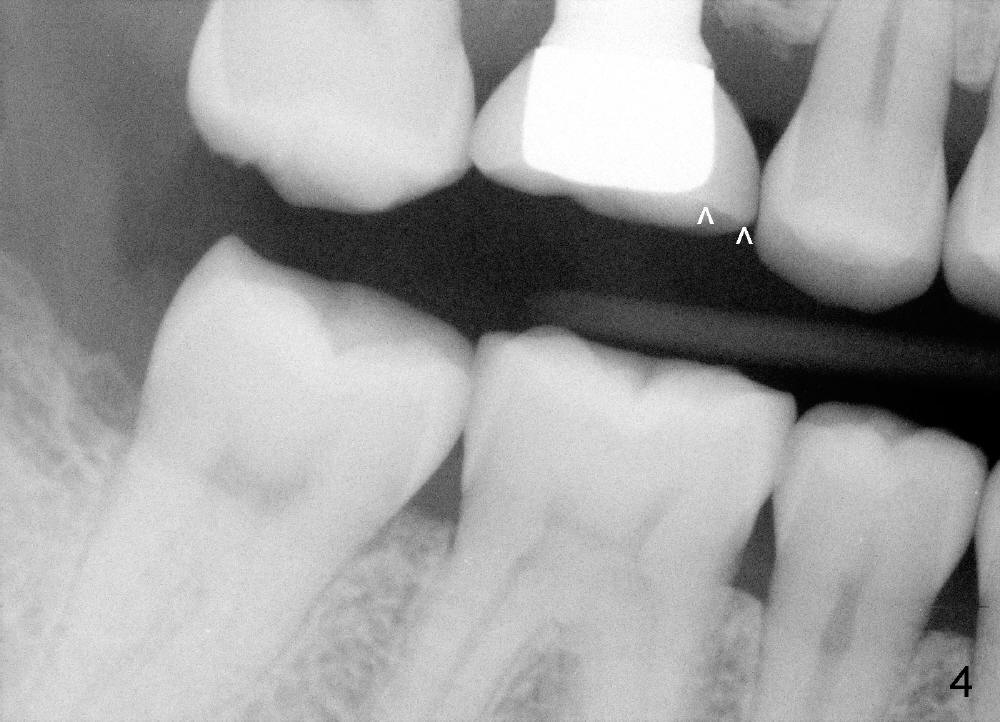

A 46-year-old man presents to clinic to fix porcelain chip over the implant crown (Fig.1 white *). The contact is loose. The patient has had history of tooth fracture, probably involving the teeth #3, 18 and 20 (Fig.2). He has habit of chewing on the right. The bone density (black *) around the implant (I) is high. All suggest bruxism.